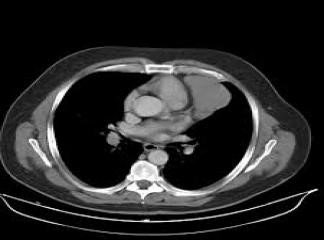

• Klinik, laborator və tomoqrafik üsullarla törəmənin təbiəti məlum olmursa rezektabelliyə görə qərar verilir (Şəkil 20). Rezektabel törəmələrdə kütlə əməliyyatla (torakoskopik və ya açıq) çıxarılır və histoloji müayinə edilir (həm diaqnostika, həm də müalicə məsələsi həll edilir). Qeyri-rezektabel törəmələrdə isə perkutan, bronxoskopik və ya torakoskopik yolla biopsiya edilir.

Şəkil 20. Divararalığında kütlə